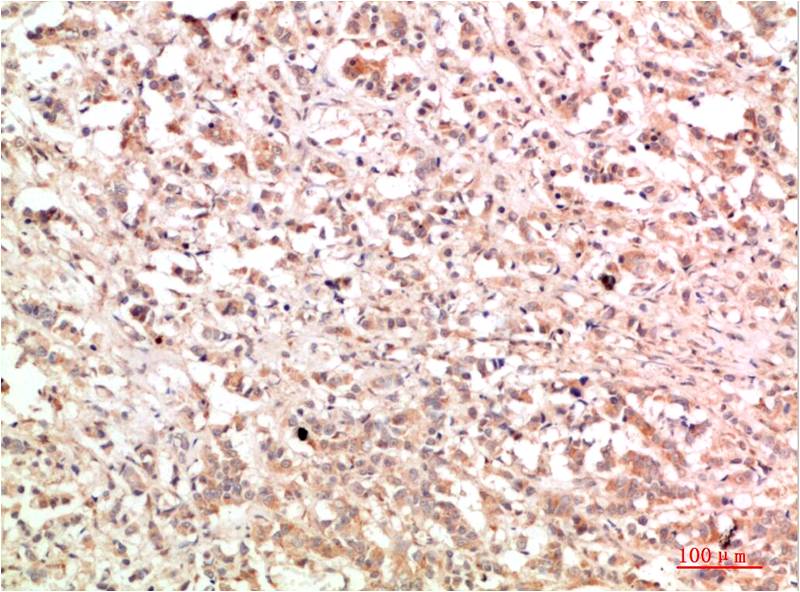

c-Jun Mouse Monoclonal Antibody(4G10)

Applications :IHC

| Recommended dilutions: | IHC 1:100-200 |

| Specificity: | The c-Jun Mouse Monoclonal Antibody can detects endogenous c-Jun proteins. |